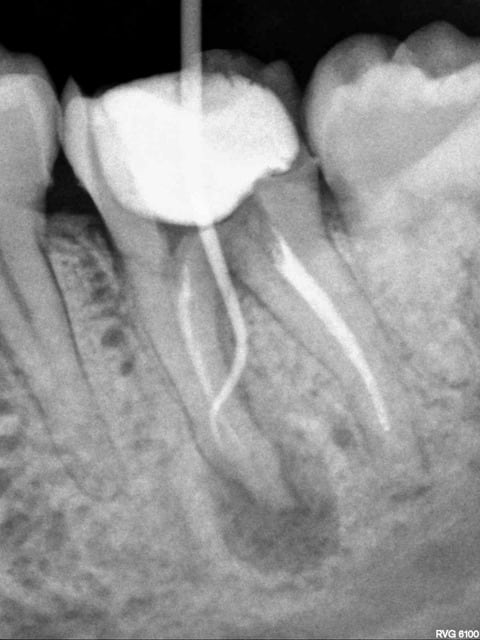

Voici les radios de l'endo exclusif. A noter la racine distale qui avait été retraitée par sa dentiste quelques semaines auparavant (la racine mésiale n'ayant pas été retraitée car elle proposait une hémisection).

J'ai éclairci l'histoire de la "deuxième couronne à 200€", car j'avais vraiment du mal à y croire ... j'ai épluché les devis, et en fait mon copain a compris que l'inlay-core à 220€ était sa prochaine couronne provisoire :D

sur la 4ème radio, c'est une perfo avec un cône?